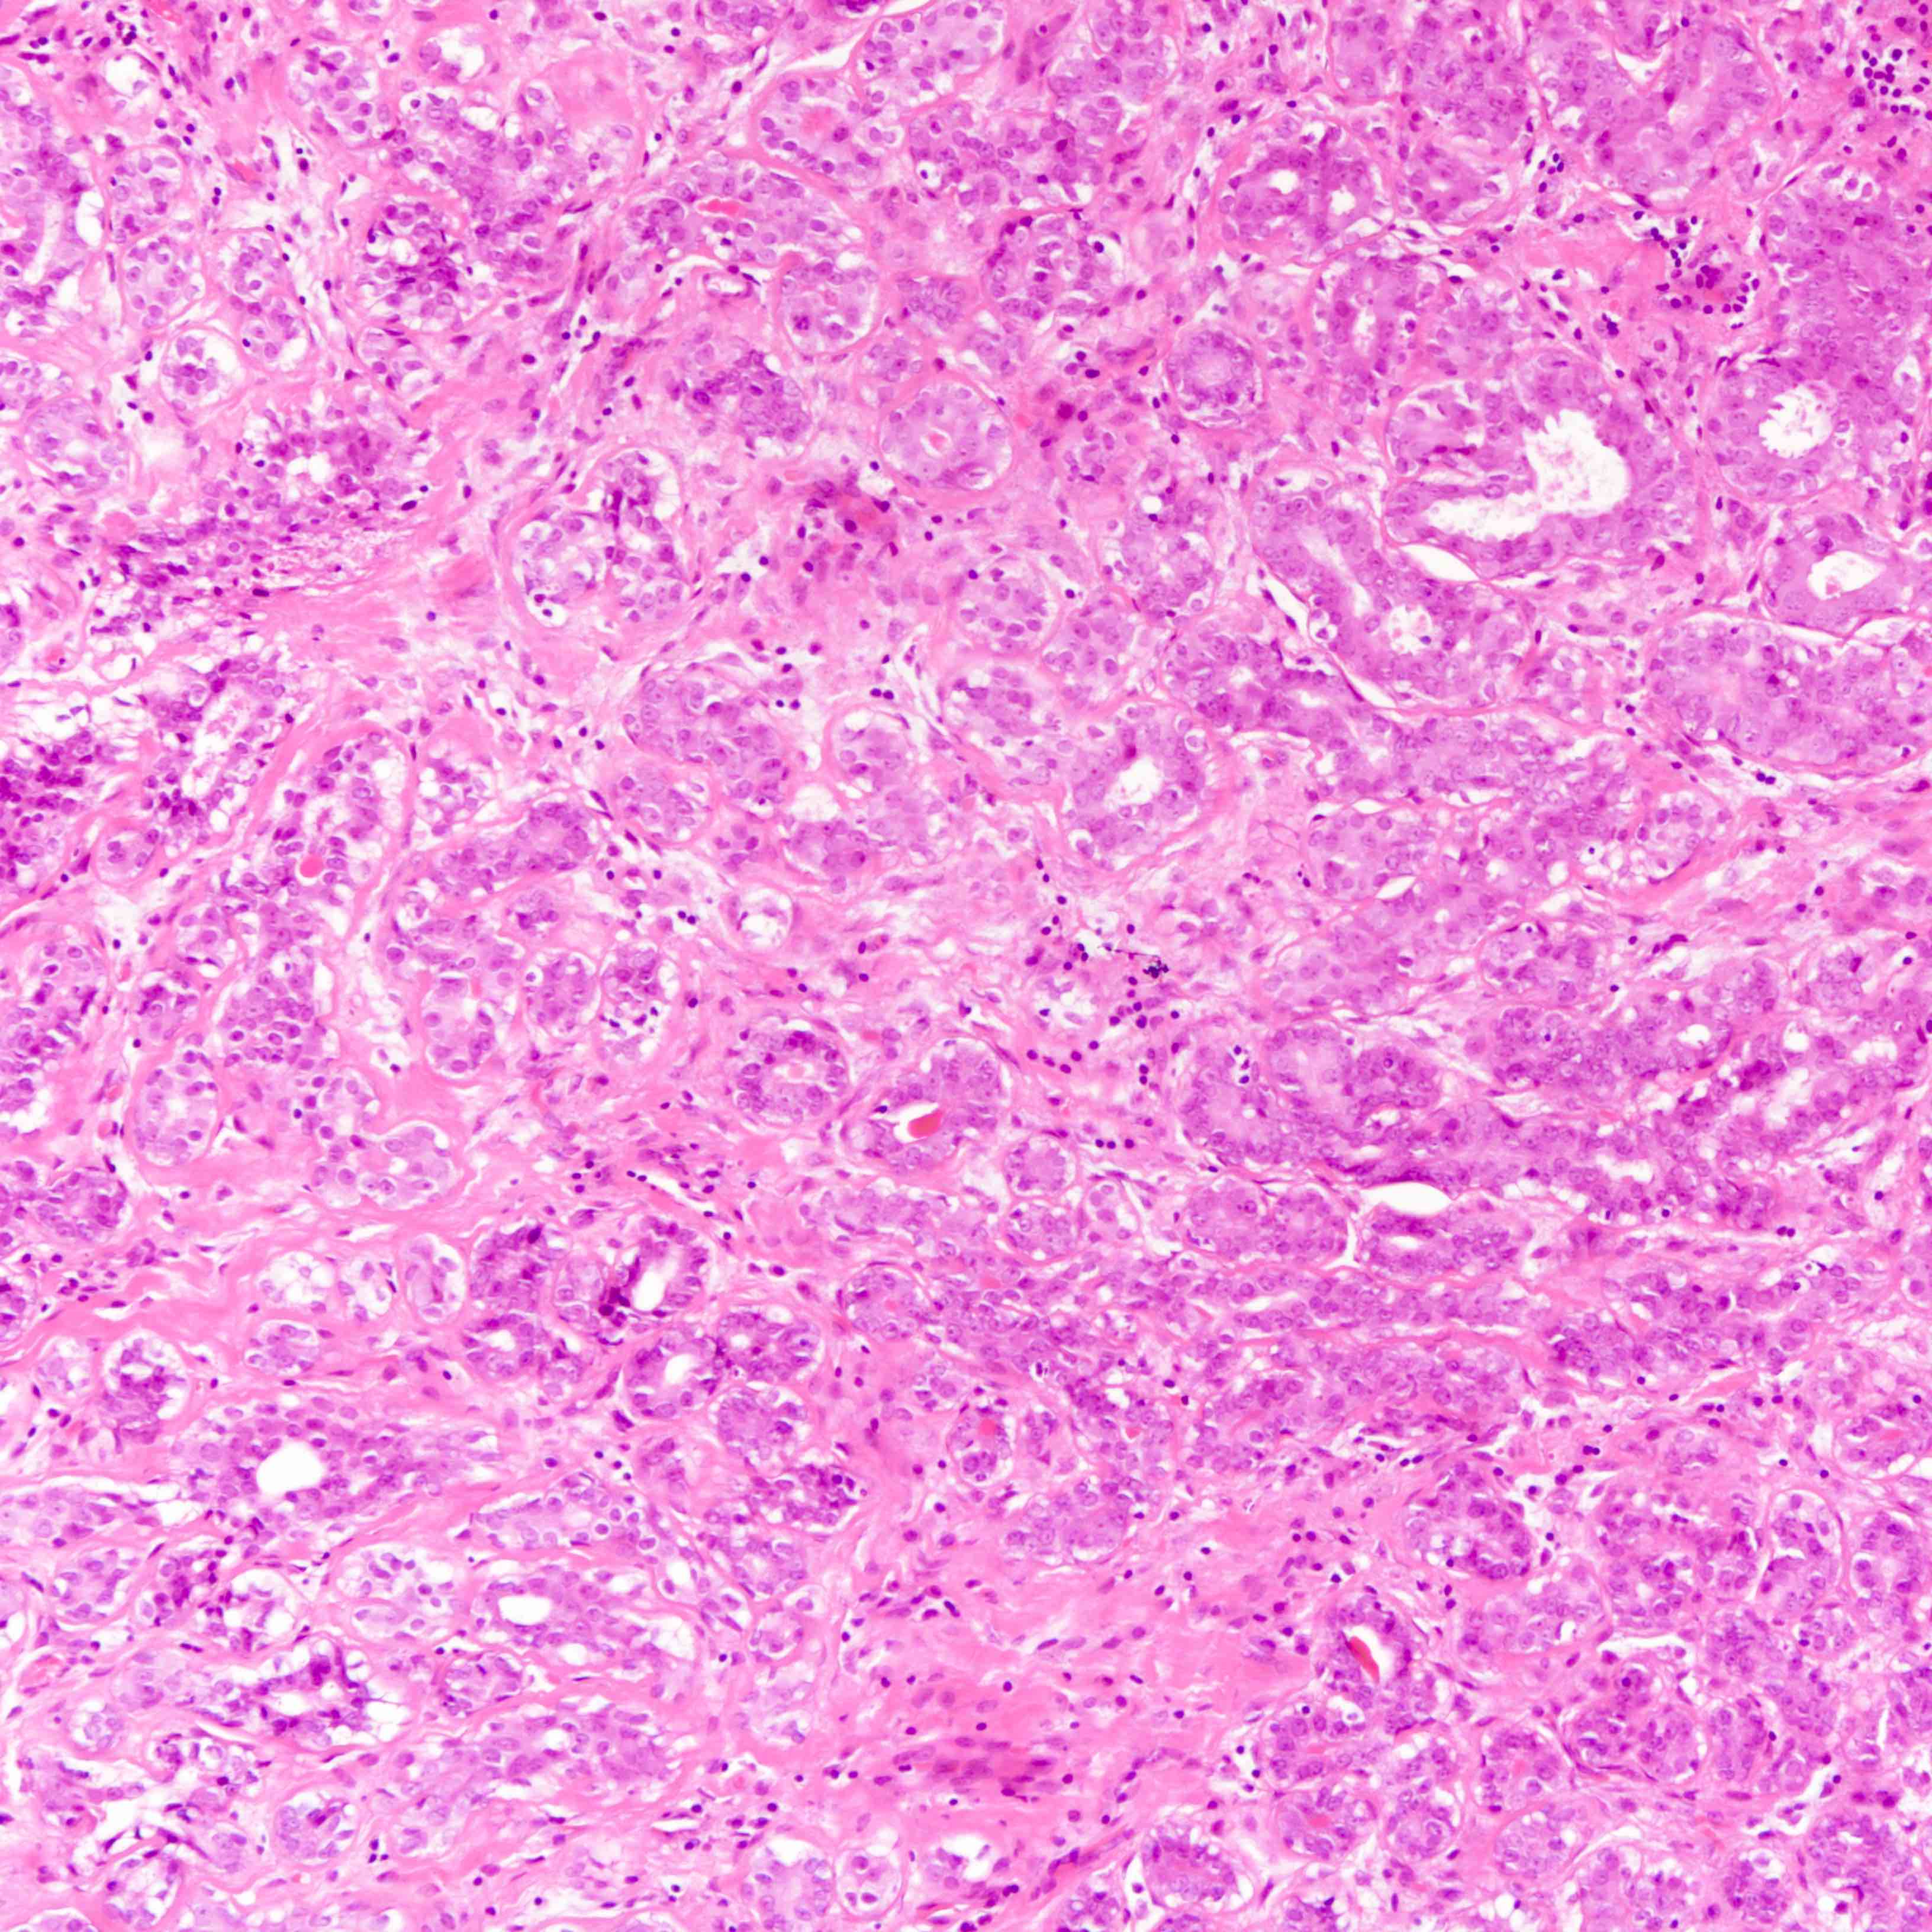

- Well defined borders

- Sparse fibrovascular stroma intervening tubules

- Small, uniform, closely packed round tubules (Clin Med Insights Pathol 2018;11:1179555718757499)

- Lined by an inner layer of luminal epithelial cells and an outer layer of myoepithelial cells

- Rare mild atypia and mitotic figures does not exclude diagnosis

- Occasional luminal eosinophilic secretion

Microscopic (histologic) images

Contributed by Joshua J.X. Li, M.B.Ch.B. and Gary M. Tse, M.B.B.S.

Contributed by Jijgee Munkhdelger, M.D., Ph.D. and Andrey Bychkov, M.D., Ph.D.